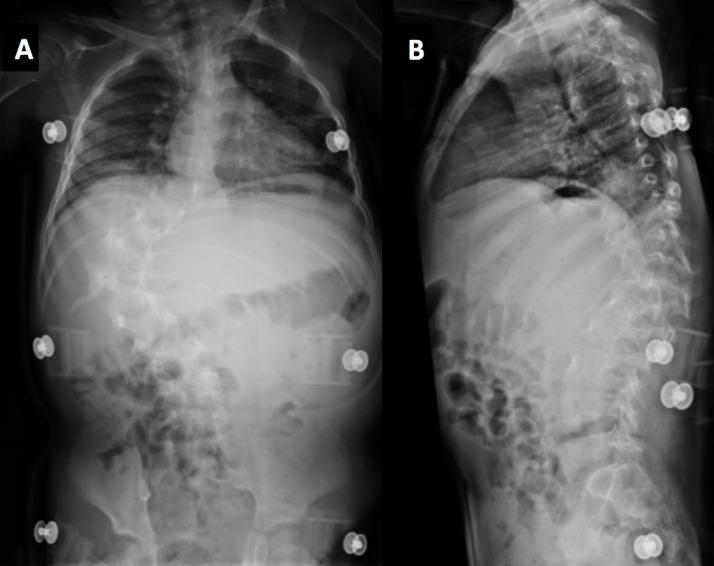

Malignant peripheral nerve sheath tumors (MPNSTs) are rare but aggressive neoplasms associated with neurofibromatosis type 1. Specifically, children with deep plexiform neurofibromas are 18 times more likely to develop MPNSTs compared to the general population. However, there is currently no standard surveillance imaging protocol for children diagnosed with deep plexiform neurofibromatosis. We present a case of a boy with neurofibromatosis type 1 and scoliosis, who later developed MPNST. This case highlights the need for more frequent surveillance imaging and the challenges of diagnosing MPNST in a patient with scoliosis. In order to facilitate early detection of malignant transformation, we suggest annual surveillance MR imaging for patients known to have deep plexiform neurofibromatosis.

摘要

恶性外周神经鞘瘤(MPNSTs)虽罕见但具有侵袭性,与1型神经纤维瘤病相关。具体而言,患有深部丛状神经纤维瘤的儿童发生MPNSTs的可能性是普通人群的18倍。然而,目前对于诊断为深部丛状神经纤维瘤病的儿童尚无标准的监测成像方案。我们报告一例患有1型神经纤维瘤病和脊柱侧弯的男孩,其后来发展为MPNST。该病例凸显了更频繁进行监测成像的必要性以及在脊柱侧弯患者中诊断MPNST的挑战。为便于早期发现恶性转化,我们建议对已知患有深部丛状神经纤维瘤病的患者每年进行监测性磁共振成像检查。